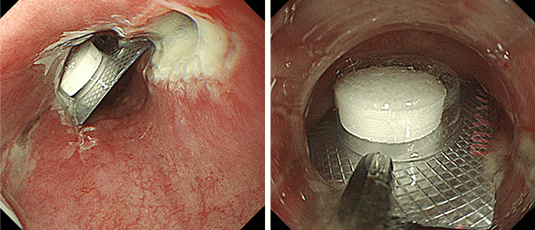

薬の殻、魚の骨、義歯、電池などを誤って飲み込んだ際に、内視鏡で安全に摘出します。

PTPシート(薬の殻)誤飲に対する鉗子を用いた回収

大腸が、がんなどで腸閉塞を来した場合に、金属製のステントを内視鏡で挿入し、通過を確保します。

下行結腸癌に対する緊急大腸ステント留置術